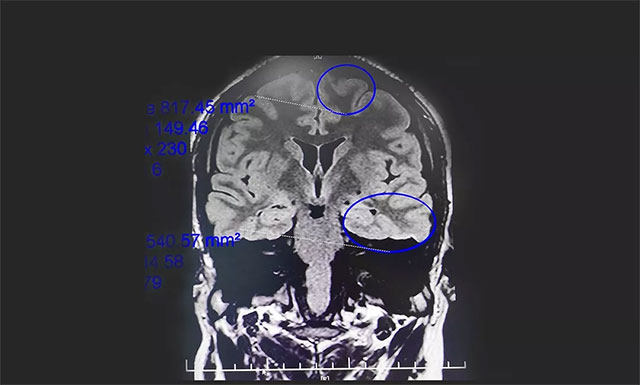

▲ 通过系列检查最终明确患者致癫灶

脑电监测崔丽华主任根据脑电图监测分析指出,患者双侧有癫痫波,左侧较为严重。磁共振检查,患者颞叶、额叶、海马结构异常。既往史显示,患者1岁时有多次高热病史,并伴抽搐。

患者经系统内科药物治疗不佳,确诊为药物难治性癫痫,经过系列检查最终明确患者致癫灶位于左侧颞叶、左侧额叶、左侧海马。手术指征明确,未见明显手术禁忌症。